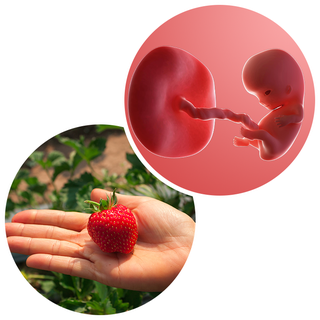

My baby at 9 weeks old 2025

My baby at 9 weeks old 2025, 9 Weeks Pregnant Week by week guide NHS 2025

My baby at 9 weeks old 2025

9 Weeks Pregnant Week by week guide NHS

9 Weeks Pregnant Baby Development Symptoms and More

9 Weeks Pregnant Your Symptoms Having an Ultrasound

Baby and You at 9 Weeks Pregnant Symptoms and Development

Week 9 for Parents Nemours KidsHealth

The Guardian is wrong this is what a 9 week old unborn baby looks

Product Item: My baby at 9 weeks old 2025